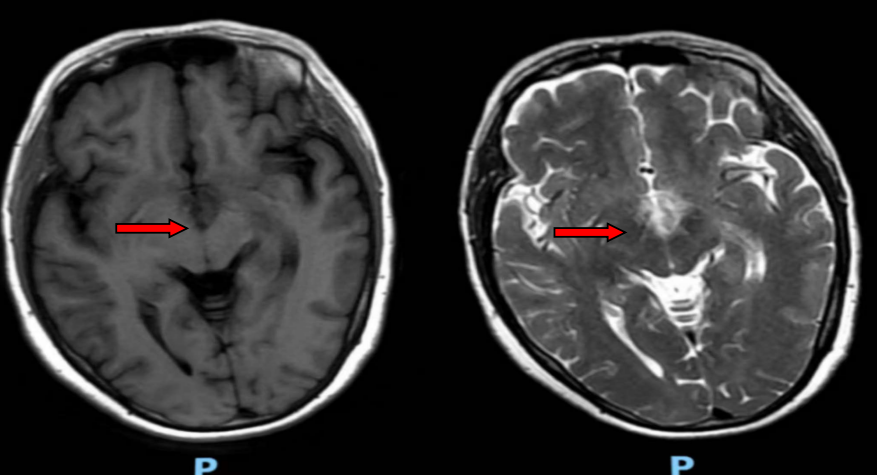

风湿免疫科欧阳楚君副主任接诊后,发现患者自身抗体谱更符合干燥综合征,需鉴别颅内感染与原发病活动,随即安排头颅MRA、腰椎穿刺及脑脊液相关检测。鉴于病情复杂,科室迅速启动多学科协作诊疗(MDT),联合神经内科、呼吸科等多科室专家会诊。结合影像学双侧丘脑及颈髓异常信号、脑脊液AQP4抗体阳性结果,最终明确诊断为“干燥综合征合并视神经脊髓炎”。

△治疗前头颅MR提示双侧丘脑内侧、灰结节脑实质异常信号影

△治疗后双侧丘脑内侧、灰结节脑实质异常信号影减轻